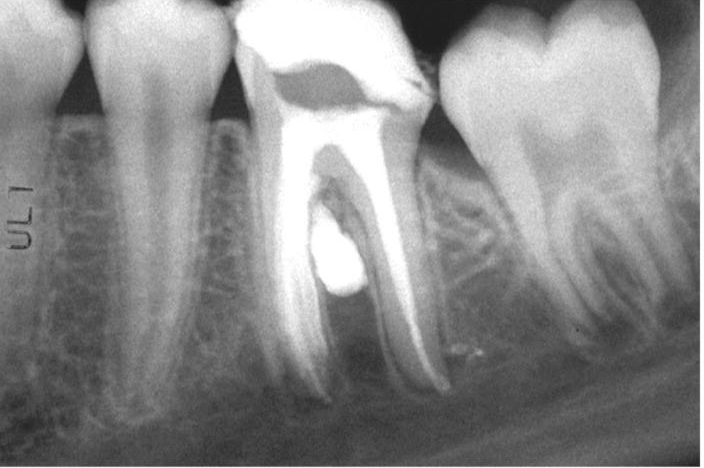

2. What Condition can be seen in this X ray regarding the tooth # 4.4.?